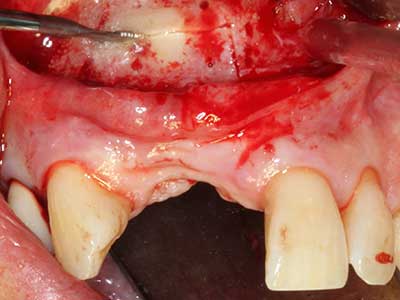

Костната тъкан е не само минерализирана структура, тя съдържа и съществено количество колагенови влакна. Това означава, че тя има не само добра компресивна сила, но и известна степен на гъвкавост, която може да се възприеме като предимство при извършване на костна аугментация. В класическата процедура по разширяване чрез костно разделяне, атрофиралият алвеоларен гребен е разделен надлъжно и внимателно разширен след достигане на подходящата остеотомна дълбочина (Фиг. 13-16), в идеалния случай без допълнително отстраняване на периостеума (Brugnami, Caiazzo et al. 2014, Stricker, Fleiner et al. 2014). Системите с винт и пластини с увеличаване на разстоянието при разширяване са доказали ефективността си при разделяне на двете костни ламели, оставайки под прага на фрактурите. В общи линии, оставащата ширина на костта от поне 3–4 mm е задължителна (Chiapasco, Zaniboni et al. 2006), за да се гарантира добра гъвкавост и достатъчно костно покритие за бъдещото поставяне на импланти. Ако е необходимо, вертикалната остеотомия на едната или двете страни може да подобри гъвкавостта. Комбинацията с допълнителни техники за аугментация, особено в букалната страна, е описана като алтернатива на класическата техника.

Процедурата по разделяне е атравматична и няма голяма загуба на пространство, използвайки пиезотриони, и няма значителна разлика между импланти в разделени челюсти и импланти в алвеоларния гребен без костен дефицит (Chiapasco, Zaniboni et al. 2006, Danza, Guidi et al. 2009). Въпреки това, важно е да има достатъчно и продължително охлаждане, особено при ограничено и дълбоко разделяне, за да се избегне термичен стрес в апикално-остеотомните зони.